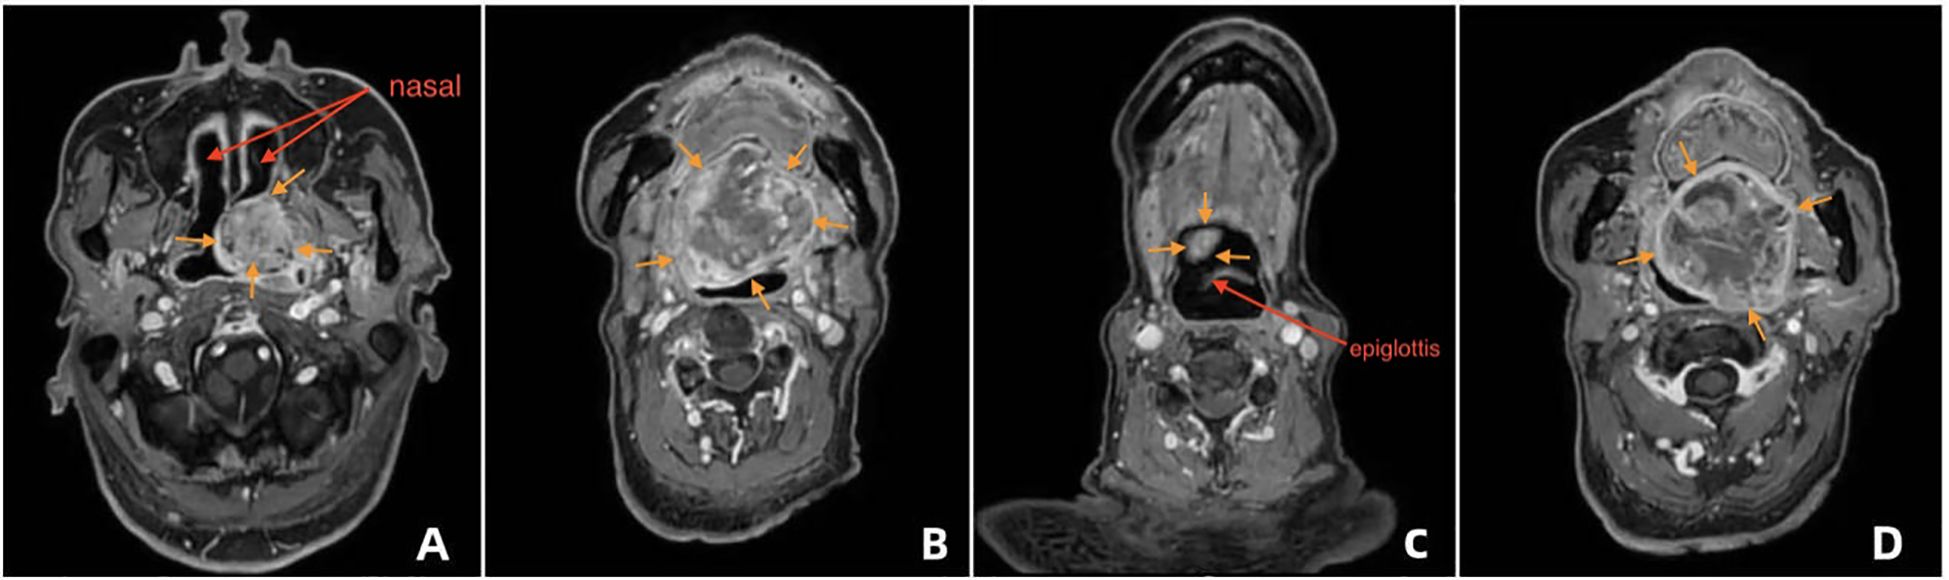

No obvious abnormalities were found in laboratory examinations. Electrocardiography revealed sinus rhythm, left axis deviation, and Q waves in leads V2–V3. Echocardiography revealed degenerative changes of the aortic valve and reduced left ventricular diastolic function. Head and neck MRI showed a soft tissue mass along the left nasopharyngeal wall, exhibiting mixed signal intensities on T1-weighted imaging (T1WI) and T2-weighted imaging (T2WI). T1WI showed mildly hyperintense signals, and T2WI revealed multiple nodular hyperintense foci with smooth margins. Contrast-enhanced scanning showed heterogeneous enhancement of septations and necrotic areas. The mass originated from the left wall of the nasopharynx, extended anteriorly into the nasal cavity (Figure 1A), obliterated the left pharyngeal recess, and descended anteroinferiorly toward the oropharynx (Figure 1B), with its inferior pole reaching the epiglottic apex. No thickening of the aryepiglottic folds was noted (Figure 1C). The mass measured approximately 7.0 × 5.3 × 5.0 cm (vertical × longitudinal × transverse dimensions), causing significant oropharyngeal narrowing. At the level of the first cervical vertebra (C1), the lesion abutted the posterior oropharyngeal wall, nearly occluding the oropharyngeal lumen (Figure 1D). Skull CT revealed a soft tissue mass on the left palate with indistinct margins protruding into the posterior nasal cavity. The left pharyngeal recess was shallow, and the lesion extended inferiorly and rightward toward the epiglottis, with peripheral calcifications. Contrast-enhanced CT showed mild heterogeneous enhancement, with a maximal longitudinal diameter of approximately 5.8 cm.

Figure 1. Preoperative imaging of the palatal mass and airway distortion (A) MRI showing the soft-tissue mass along the left nasopharyngeal wall protruding into the nasal cavity with heterogeneous signal and contrast enhancement. (B) MRI sagittal view illustrating the mass extending downward toward the oropharynx and near the epiglottic area. (C) MRI showing preserved glottic structures with no thickening of the aryepiglottic folds. (D) CT scan illustrating the mass boundary, calcifications at the edge, and the inferior extent toward the epiglottic region, with marked narrowing of the oropharyngeal lumen at the C1 level.